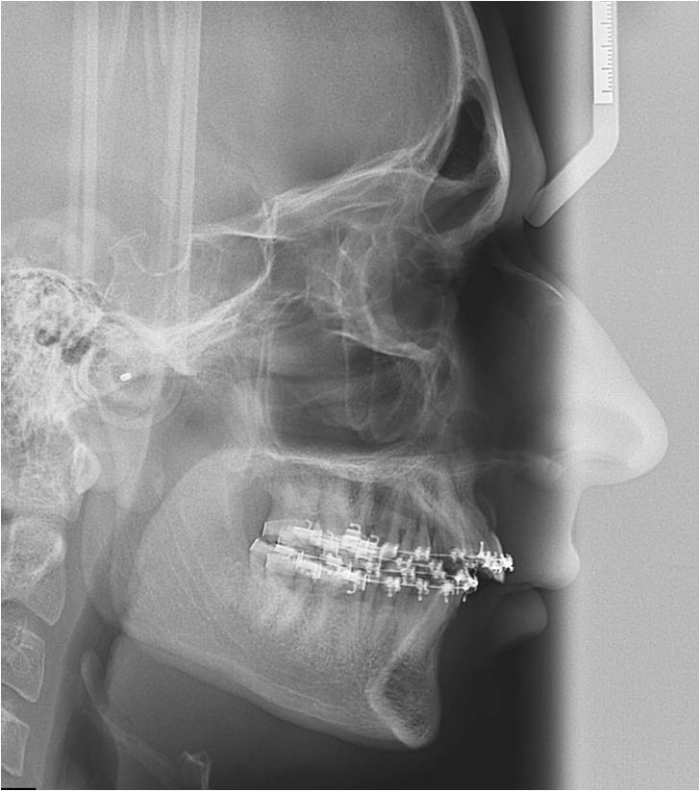

Telerradiografia inicial